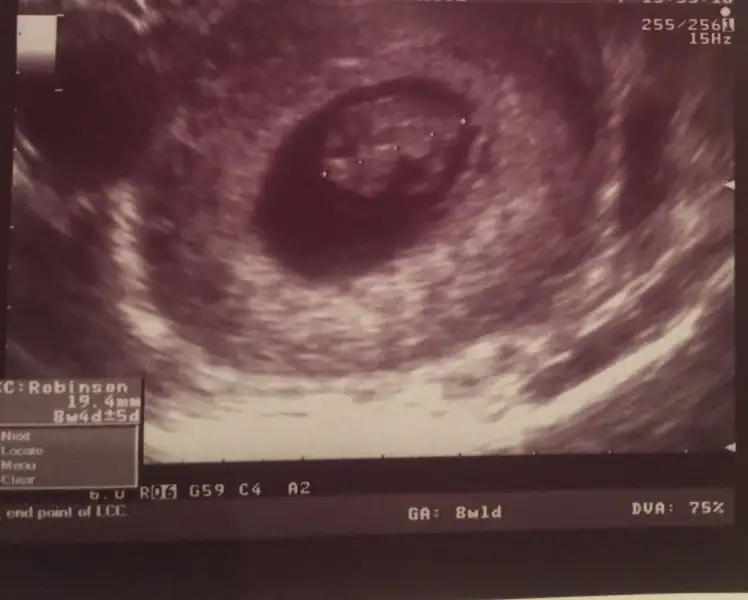

buna gore erkek canım. benım karından boyleydı doktor kıza benzıyor dedı. kesındegıl benımkıde ama kesnlesırse teorı bnde tuttuEki Görüntüle 1939188 Eki Görüntüle 1939187 Kizlar banada baksanizaa altan utrasyon yani vajenden

Kızlarr nerdesiniz cevap yok muEki Görüntüle 1939127 Eki Görüntüle 1939128 Kızlar bana da bakar mısınız karından ultrason ve üstteki 9 hafta alttaki 7 haftalık